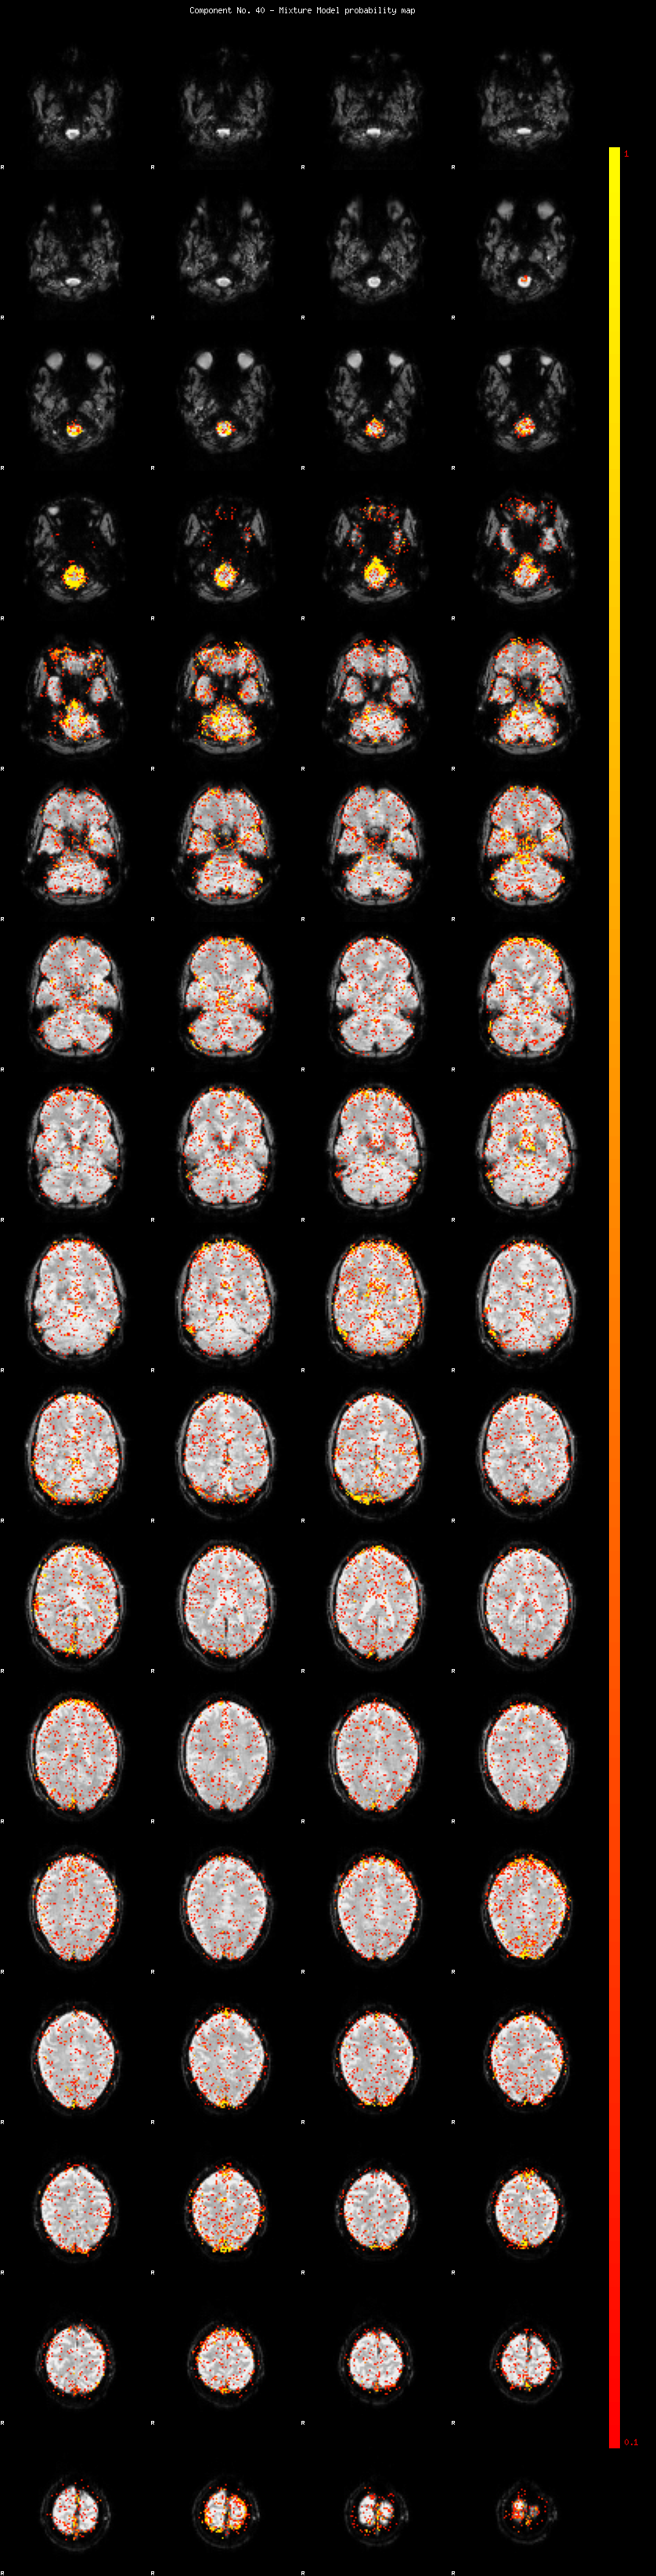

IC_40 Mixture Model fit

Means : 0.000000 2.615925 -2.376638

Vars : 1.000000 2.475756 1.694446

Prop. : 0.934298 0.032385 0.033316